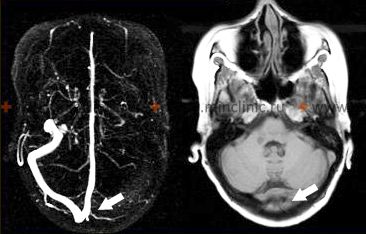

მრ ვენოგრაფია აჩვენებს მარცხენა განივი სინუსის თრომბოზს. მიუხედავად იმისა, რომ ვასკულიტმა *შეიძლება* დააზიანოს ვენები/სინუსები, ის ძირითადად აზიანებს არტერიებს. ვენური თრომბოზი არის განსხვავებული მდგომარეობა, რომელსაც ზოგჯერ იწვევს ინფექცია ან ანთება. - თავის ტვინისა და ლეპტომენინგეალური გარსის ბიოფსია: ითვლება საბოლოო სადიაგნოსტიკო ტესტად, განსაკუთრებით საეჭვო PACNS-ის დროს, როდესაც სხვა მიზეზები გამოირიცხება [1, 2]. ბიოფსია, რომელიც აჩვენებს სისხლძარღვების კედლების ტრანსმურალურ ანთებას, ადასტურებს დიაგნოზს [1]. თუმცა, ის ინვაზიურია პოტენციური რისკებით და შედეგი შეიძლება იყოს შეზღუდული დაავადების კეროვანი ბუნების გამო (შერჩევის შეცდომა/sampling error) [1, 2]. ბიოფსია, როგორც წესი, მიზანმიმართულია იმ უბნისკენ, რომელიც მრტ-ზე ანომალიას აჩვენებს [2].